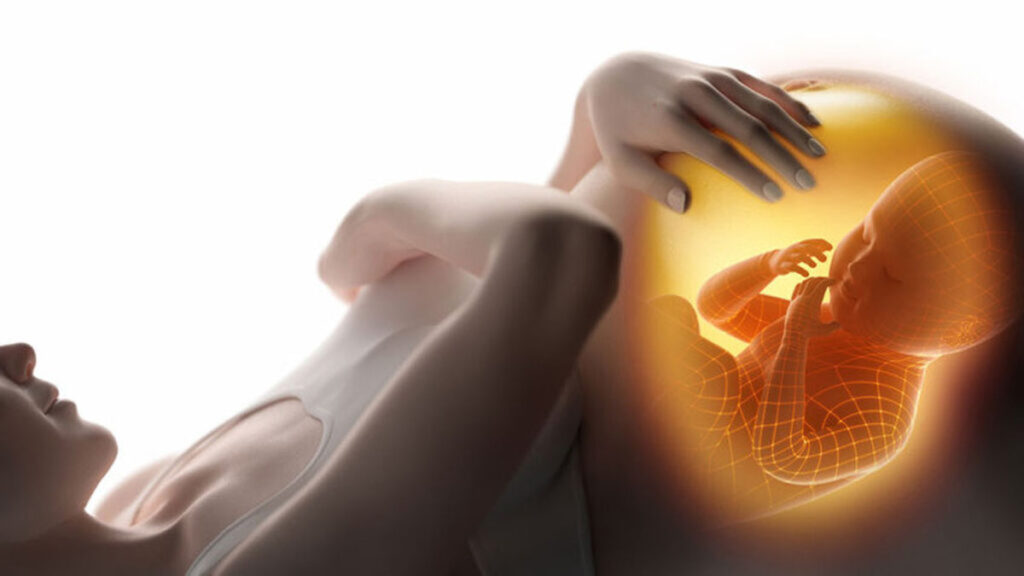

Aan het begin van de zwangerschap zorgt het hormoon progesteron ervoor dat er slijm wordt verzameld in de baarmoedermond. Dit slijm gaat daar verdikken tot een taaie massa. De slijmprop is dus helemaal geen prop, maar meer een soort dik, taai slijm van zo’n twee tot drie centimeter.

De slijmprop is bedoeld om je baarmoeder af te sluiten tijdens je zwangerschap zodat er geen bacteriën of andere schadelijke stoffen bij je baby kunnen komen. Hij houdt echter ook sperma tegen om te voorkomen dat er nog een tweede eicel bevrucht kan worden, mocht er toevallig nog een tweede eicel loskomen tijdens je zwangerschap.

Hij zit er dus niet voor niets, maar als de bevalling is ingezet, wordt de slijmprop overbodig en zal er vanzelf uitvallen op het moment dat je baarmoedermond wat wijder wordt. Je vindt hem wellicht tijdens het douchen of gewoon in je onderbroek. Schrik niet als er een klein beetje bloed in het slijm zit.